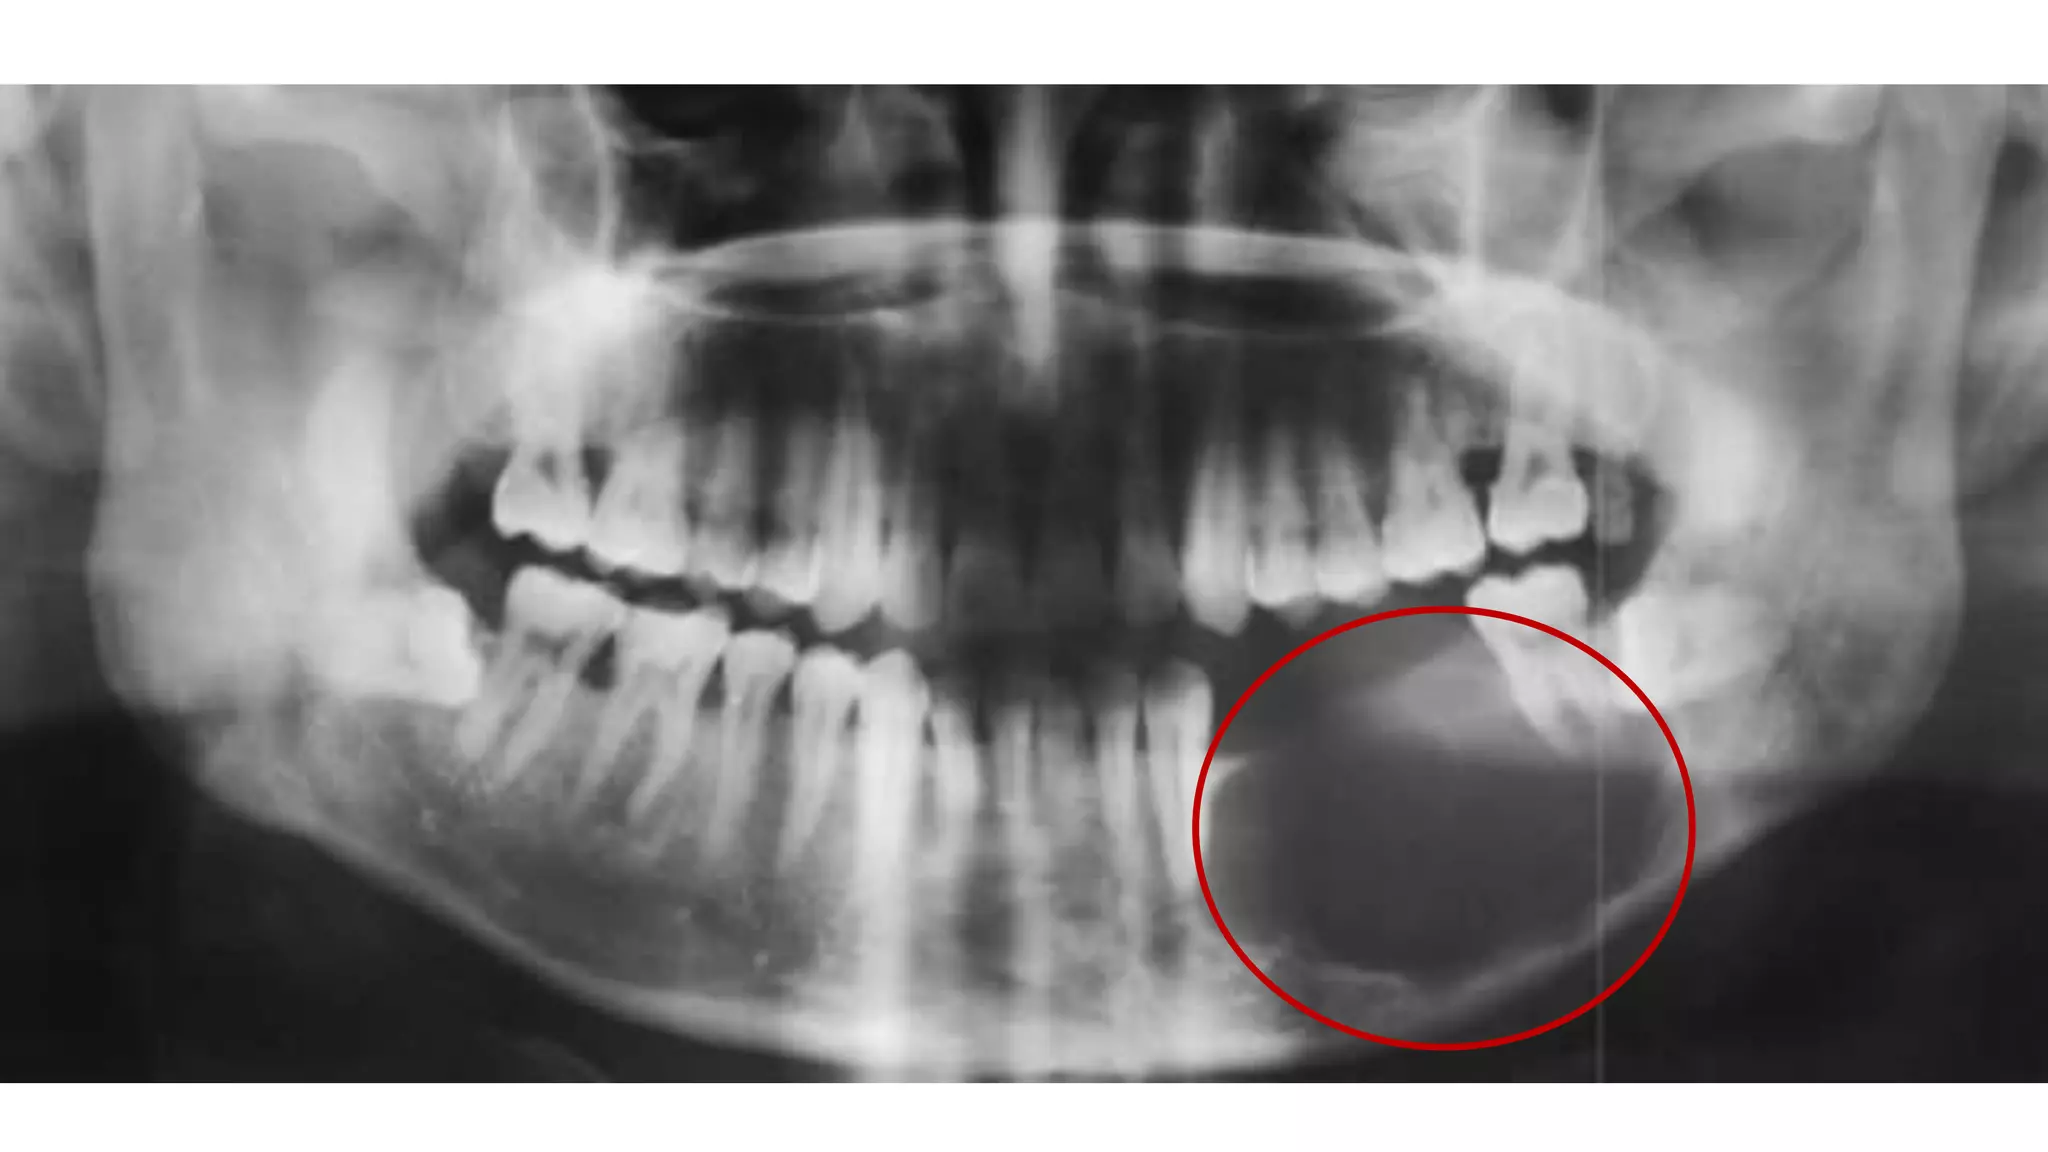

АМЕЛОБЛАСТОМА

Амелобластома – это доброкачественная одонтогенная опухоль челюстно-лицевой

локализации, вызывающая деструкцию костной ткани. По мере развития

амелобластомы возникает асимметрия лица, происходит постепенная деформация

челюсти, расшатывание и смещение зубного ряда

АМЕЛОБЛАСТОМА Амелобластома – этодоброкачественная одонтогенная опухоль челюстно-лицевой локализации, вызывающая деструкцию костной ткани. По мере развития амелобластомы возникает асимметрия лица, происходит постепенная деформация челюсти, расшатывание и смещение зубного ряда